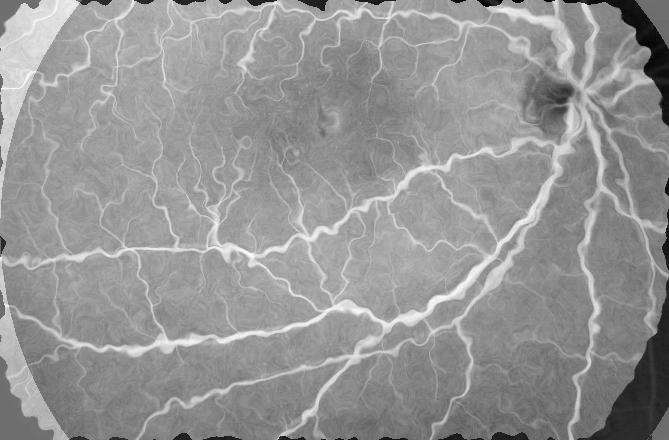

Table 1 shows the registration performance for , our proposed method, and compared with the following methods: - the CNN based registration method of [28]; - an iterative NMI based registration method [85, 86, 87, 88, 89, 90, 91]; and - without deformation consistency constraints. has the best performance across all metrics. Figure 2 shows registration results for retinal images. registers the images closest to the original and is able to recover most deformations to the blood vessels, followed by , , and . It is obvious that deformation reversibility constraints significantly improve registration performance. Note that the fundus images are color while the FA images are grayscale. The reference image is a grayscale version of the fundus image.

| (a) | (b) | (c) | (d) | (e) | (f) | (g) | (h) |